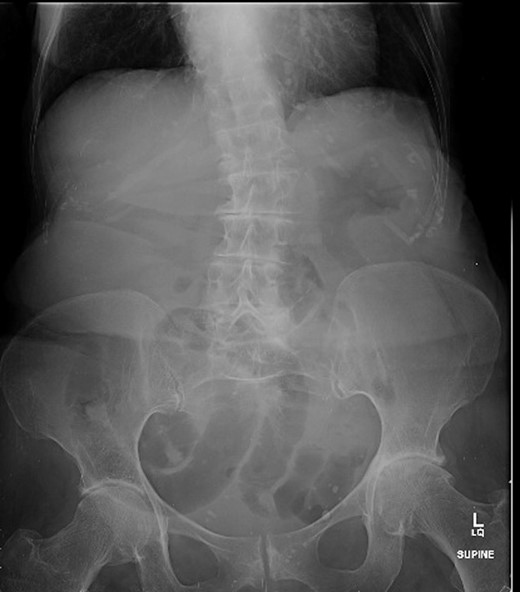

A 88-year-old woman presented to the ED with abdominal pain, vomiting, right hip pain and diarrhoea. Medical co-morbidities include ischaemic heart disease, hypertension and bilateral osteoarthritis of the hip. Her surgical history includes three Caesarean sections, open cholecystectomy, umbilical hernia repair and left mastectomy for breast cancer. A computed tomography (CT) abdomen revealed small bowel obstruction due to the right OH (Fig. 1) and evidence of a small left OH. A trial of conservative management was made for patient due to her age, multiple co-morbidities and patient's wishes. Bowel obstruction resolved with conservative management. The patient re-presented 1 month later with small bowel obstruction and pain radiating down medial left leg. There were no clinical signs of intestinal ischaemia. Abdominal x-ray was consistent with small bowel obstruction (Fig. 2) and CT abdomen revealed transition point at left OH (Fig. 3). A decision was made to proceed with midline laparotomy and bilateral OH repair. Intra-operatively, there was a large right OH containing a small bowel, which was reduced, and a bard polypropylene mesh plug inserted into the defect and fixed with prolene interrupted sutures. The left OH was smaller and was repaired primarily with prolene. The patient made an unremarkable recovery, and she was discharged 3 days after the operation. No recurrence was noted within a year of follow-up.

Abdominal x-ray showing dilated small bowel loops and severe osteoarthritis changes in both hips.